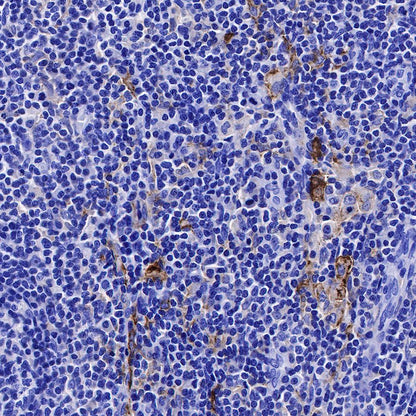

IHC shows positive staining in paraffin-embedded human placenta. Anti-CD169 antibody was used at 1/250 dilution, followed by a HRP Polymer for Mouse & Rabbit IgG (ready to use). Counterstained with hematoxylin. Heat mediated antigen retrieval with Tris/EDTA buffer pH9.0 was performed before commencing with IHC staining protocol.